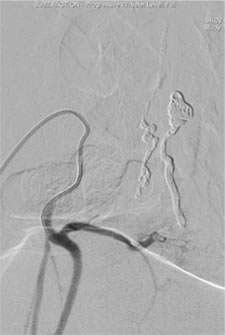

Depending on the lesion, the best treatment plan changes. For intramedullary AVMs, partial or palliative treatment is sometimes an option since complete obliteration may carry a much higher chance of causing neurological deficits than conservative management or partial treatment (Figure 3).

Figure 3: A palliative / partial Catheter Treatment for a Spinal AVM.